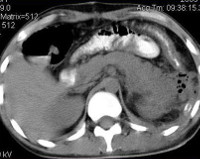

В сомнительных и трудных случаях назначают КТ забрюшинного пространства. Данное исследование с большей точностью помогает определить этиологию болезни, местоположение флегмоны и изменения со стороны соседних органов.